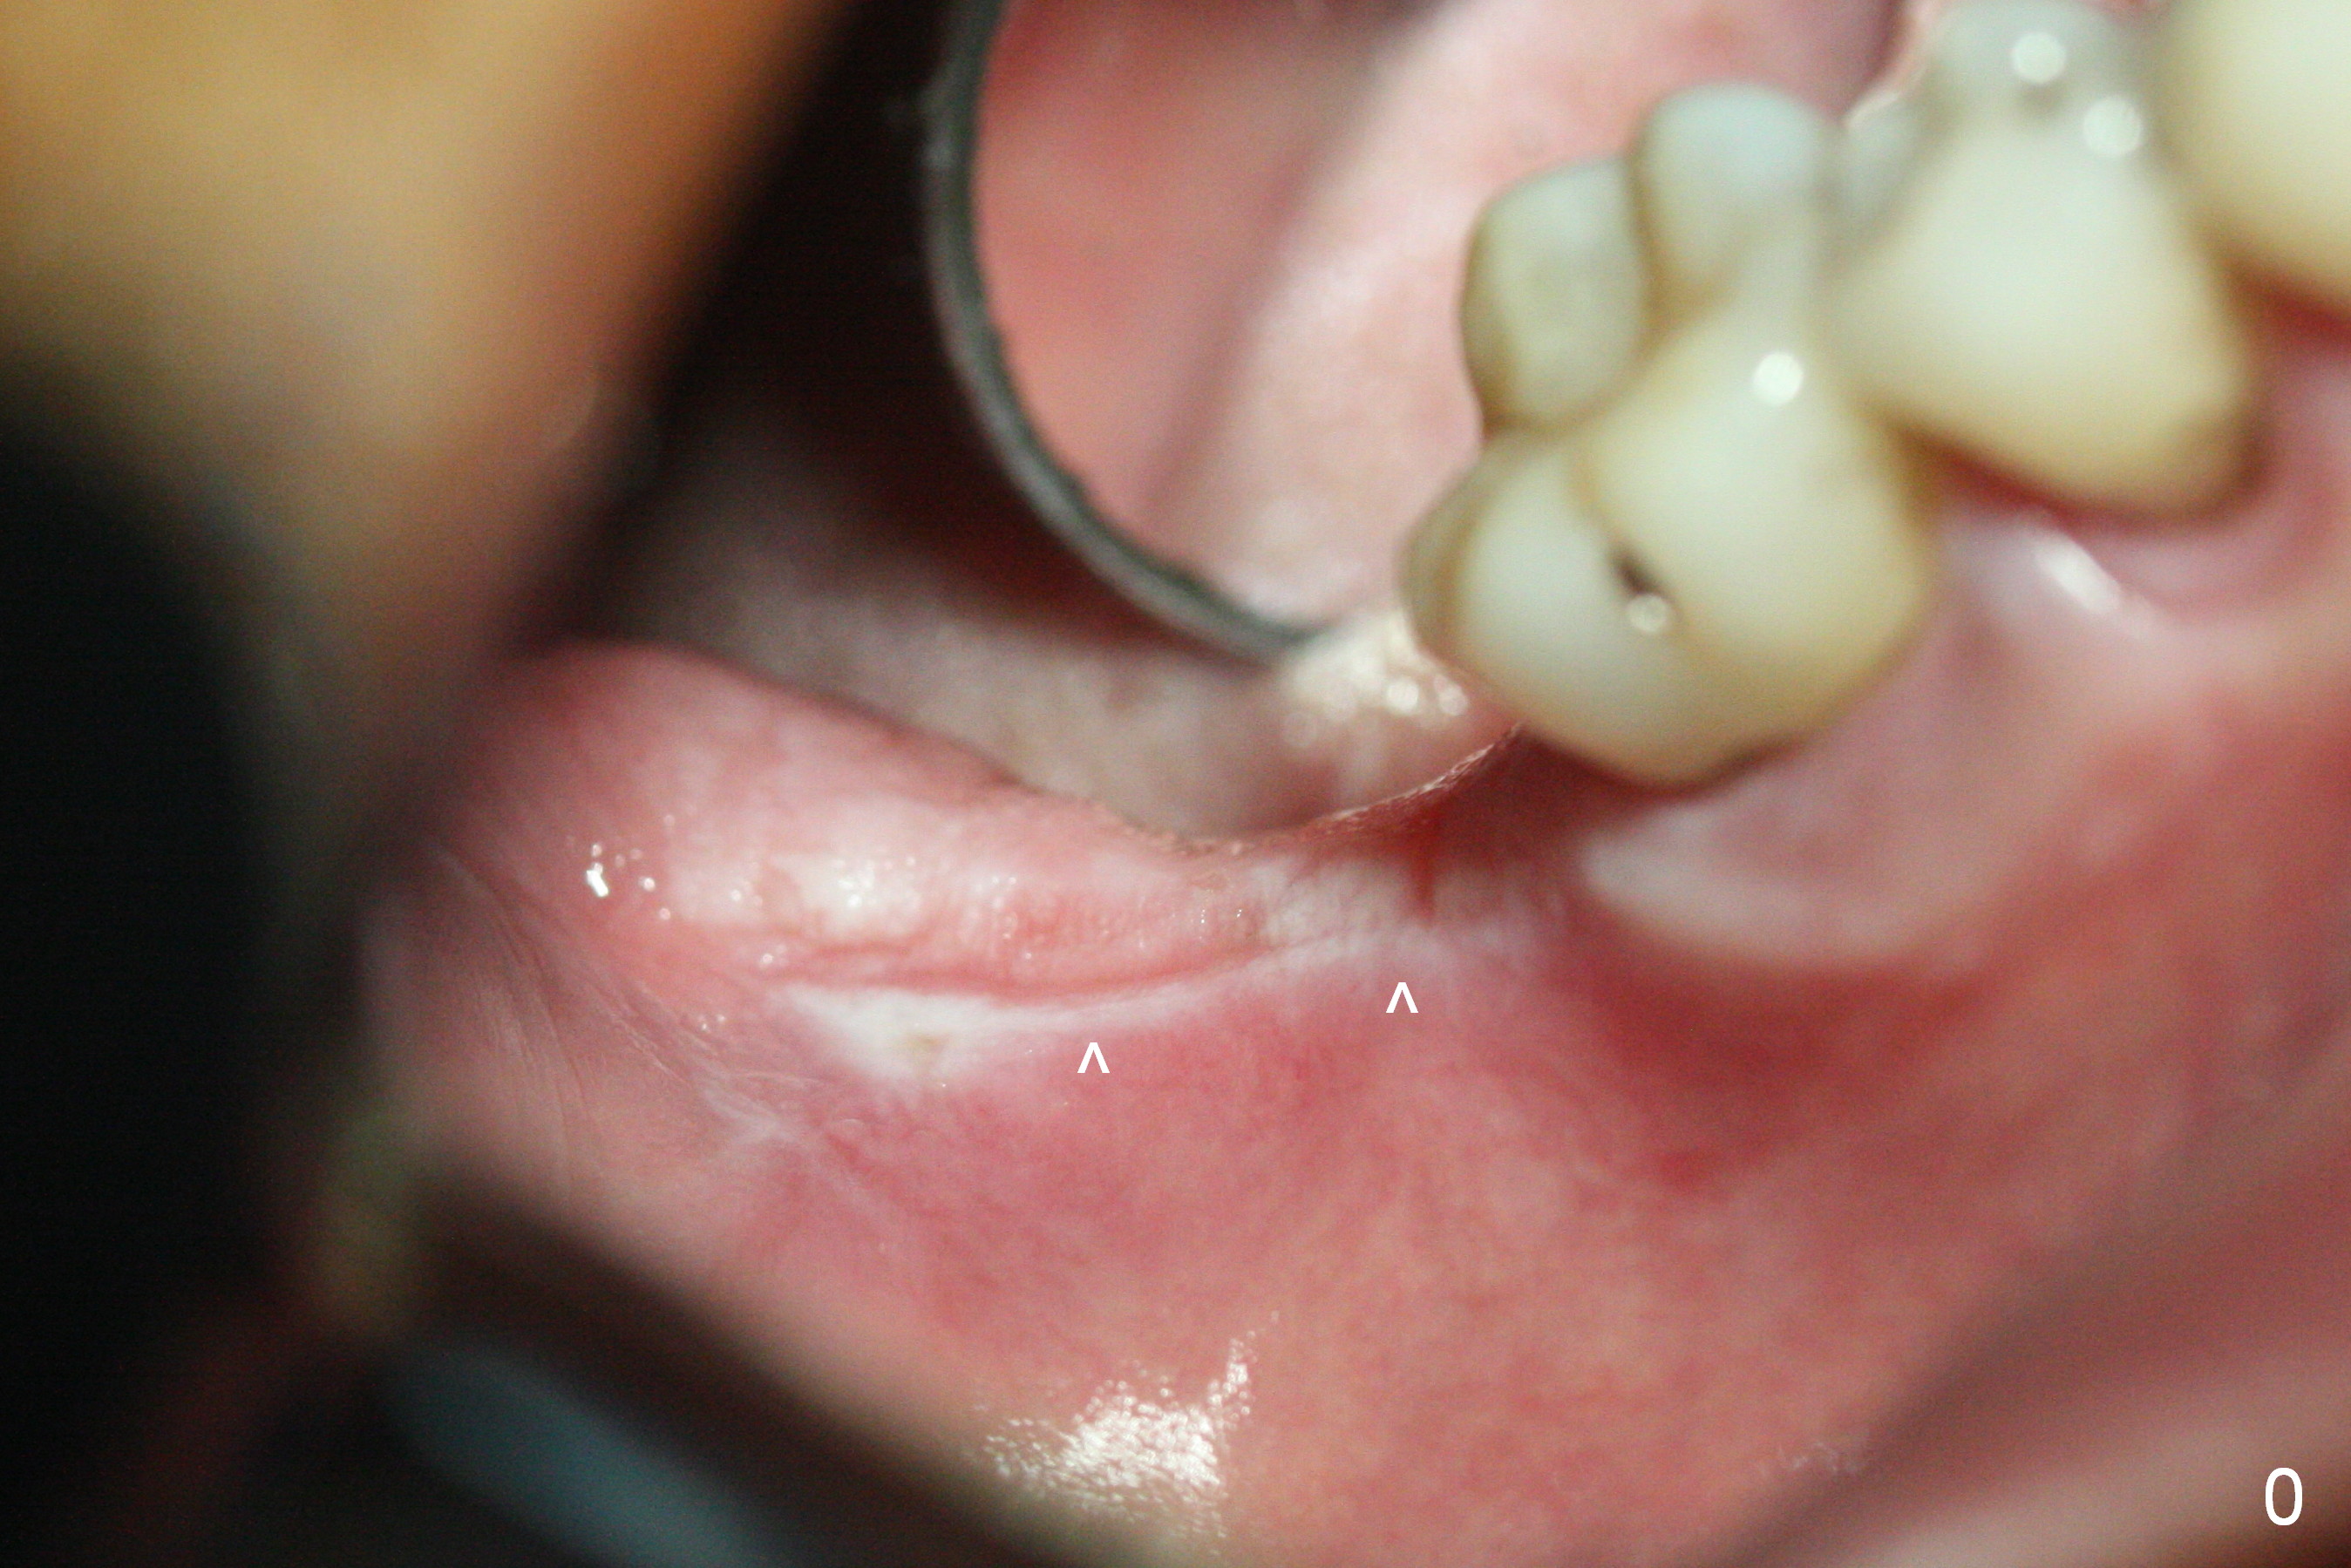

The leukoplakia at the sites of #31 and 32 is most likely related to smoking and the supraerupted teeth #1 and 2 (Fig.0 ^). After osteotomy for 11.5 mm at #31 (Fig.1), it appears that the bone height is not as much as expected. The last two drills for sequential osteotomy are 4.3x13 and 4.8x11.5 mm. A 5x11.5 mm UF implant is placed slightly subcrestal with insertion torque > 50 Ncm (Fig.2). Following placement of 6.5x2 mm healing abutment, the opposing tooth needs adjustment for height. Orthodontic intrusion of the opposing tooth is scheduled 2 days later. It is accidental to find root fracture of the mesial root of the tooth #30 (Fig.1 <). There is minimal bone resorption coronally 5 months postop (Fig.3). A provisional is fabricated at #31 to assist in intrusion of the tooth #2. A crown is cemented 11.5 months postop (Fig.4); the leukoplakia at #31 seems to lessen. The tooth #30 is lost during the pandemic, followed by looseness of the crown and abutment at #31. When the complex is reseated, the occlusal scheme is changed, suggesting incomplete seat of the abutment earlier (Fig.5).